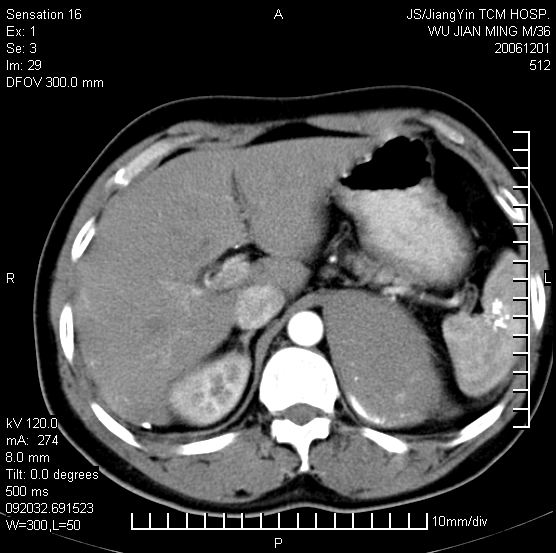

以下是引用dyqct在2006-12-1 21:17:00的发言:[br]左心缘旁及后肋膈窦区见巨大椭圆形混杂密度肿块,周围见大小不等斑片状钙化,内部无强化,周围包膜轻度强化,心脏明显受压变形,即明显占位效应,肿块广基与心包、膈相连。肝、脾内、肝门见多数小结节状钙化影。[br]考虑:1、左心缘旁及后肋膈窦区慢性包裹性胸膜炎(结核性);[br] 2、肝、脾及肝门淋巴结核已钙化。[br]

以下是引用zrs在2006-12-2 17:28:00的发言:[br]肺内、肝脾内虽有钙化,但不支持结核性胸胸膜炎包裹,而支持寄生虫感染![br][br]

以下是引用zyx168在2006-12-2 10:10:00的发言:[br][br]肝脾肺内多发钙化灶